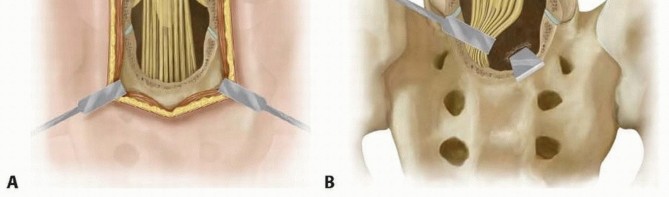

Decompression

The nerve roots of L5 and S1 are identified, and a wide decompression of the L5/S1 roots is carried out bilaterally (

TECH FIG 2A

).

TECH FIG 2 • A. A wide laminectomy is performed by removing the posterior elements of L5 and S1, and adequate decompression of the nerve roots is done. B. The dura is retracted gently, and a sacroplasty is then performed to take pressure off of the dura by using an osteotome. The dura and neural elements over the sacrum are gently retracted, and a sacroplasty is done using an osteotome or a highspeed diamond burr (

TECH FIG 2B